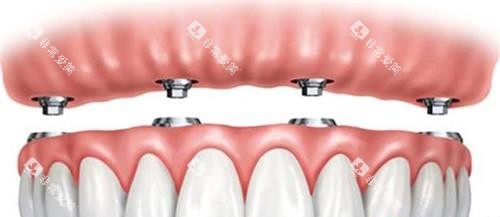

机构采用靠前的3D智能化种植技术,结合CBCT影像分析,确保种植位置精密无误。

机构采用德国BEGO、美国百康等高端种植体,结合智能化导板设计,确保种植牙既稳固又自然。